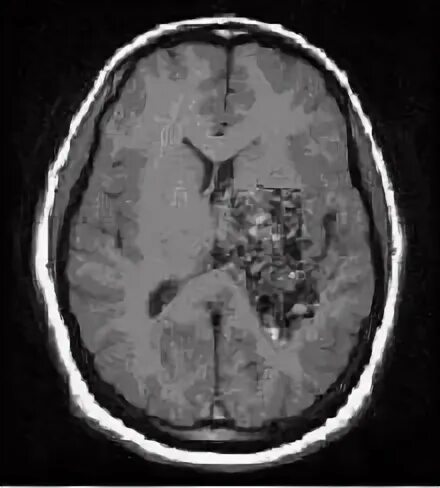

Что такое мальформация головного мозга